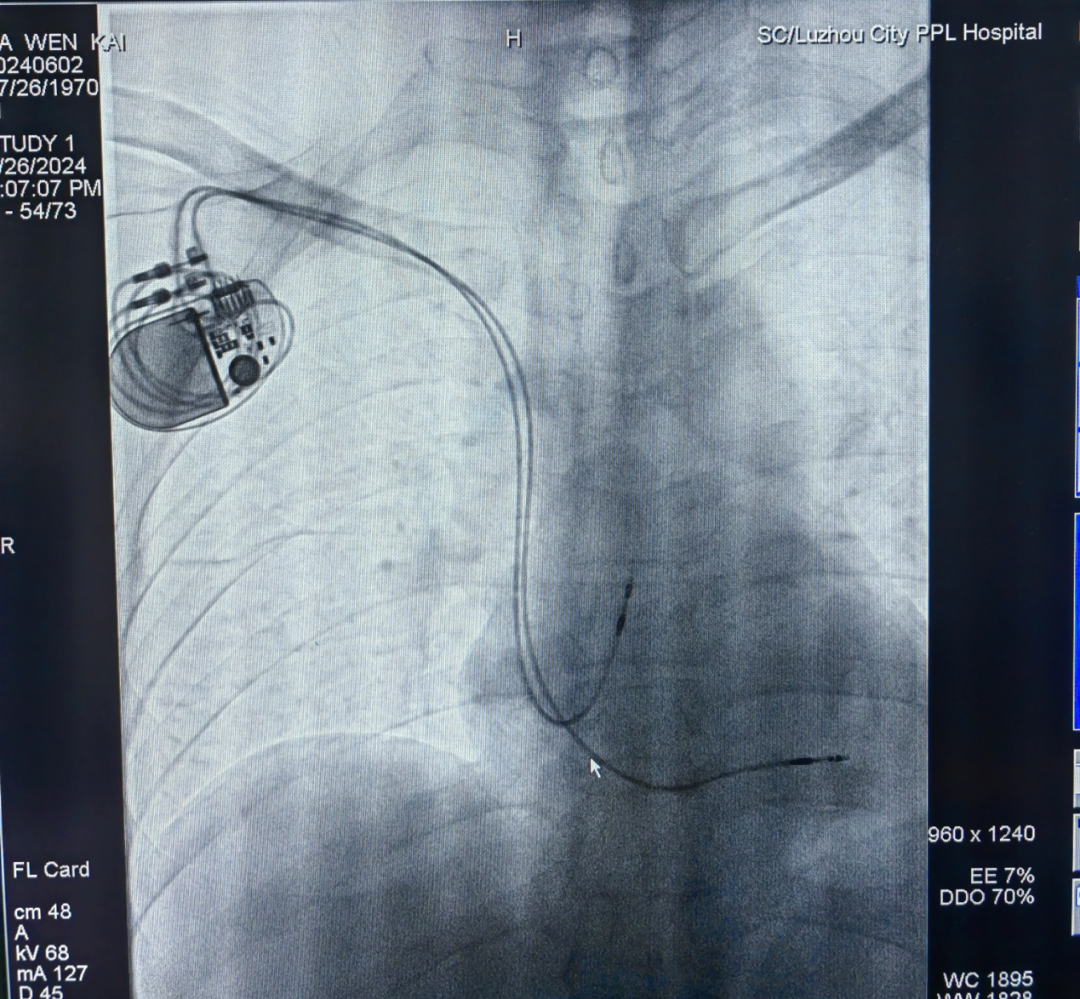

由于马大叔身患尿毒症,长期透析,左侧上肢存在动静脉瘘,为避免影响静脉回流,林强主治医师与高毅滨主任医师决定,在植入永久双腔起搏器时,选择右侧植入(常规为左侧植入)。这一非传统路径的手术操作难度虽高于常规左侧植入,但成功保障了患者的长期生活质量。

永久起搏器植入影像